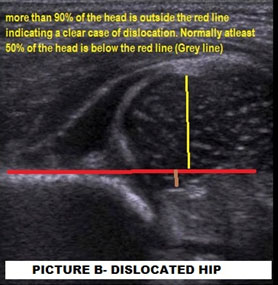

USG is an essential investigation before the ossification of the femoral head, which happens at the age of 4-6 months. It is investigator dependent. An experienced operator needs to perform as “a normal hip might be made to look abnormal, and an abnormal hip cannot be made to look normal.” It helps to see the acetabular bony anatomy, femoral head, labrum (which is the lining of the mouth of the acetabulum), and the hip capsule. If done within 4-6 weeks of birth might increase the number of false positives- so ideal time to obtain a USG hip in a questionable hip is 4-6 weeks after birth. It is not cost-effective for routine screening of patients. It is useful in monitoring of reduction of a hip after Pavlik Harness usage

Two numbers to remember is- an Alpha angle, which should be more than 60 degrees, and coverage should be more than 50%.